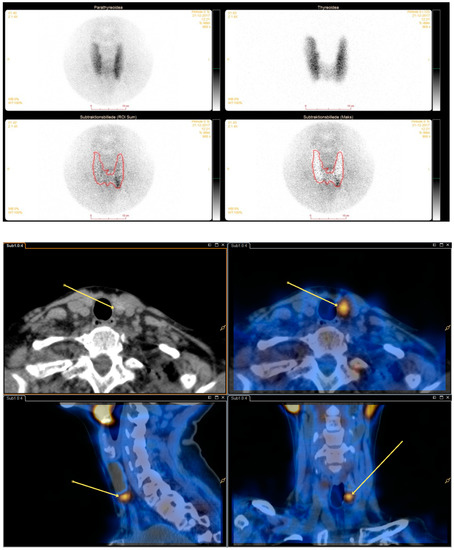

Background: Adding subtraction single-photon emission computed tomography/computed tomography (SPECT/CT) to dual isotope (I-123 and Tc-99m-sestamibi) subtraction parathyroid scintigraphy is not widely implemented. We aimed to assess the added value of dual isotope subtraction SPECT/CT over single isotope SPECT/CT as an adjunct to dual [...] Read more.

Background: Adding subtraction single-photon emission computed tomography/computed tomography (SPECT/CT) to dual isotope (I-123 and Tc-99m-sestamibi) subtraction parathyroid scintigraphy is not widely implemented. We aimed to assess the added value of dual isotope subtraction SPECT/CT over single isotope SPECT/CT as an adjunct to dual isotope planar pinhole subtraction scintigraphy. Methods: Parathyroid scintigraphies from 106 patients with an estimated total of 415 parathyroid glands who (1) were diagnosed with primary hyperparathyroidism, (2) underwent dual isotope subtraction scintigraphy in the Department of Nuclear Medicine, Gentofte Hospital, Denmark throughout 2017 and (3) underwent subsequent parathyroidectomy, were included. The original dual isotope planar pinhole subtraction plus dual isotope subtraction SPECT/CT (dual/dual method) exams were retrospectively re-evaluated using only Tc-99m-sestamibi SPECT/CT (dual/single method). Statistics were calculated per parathyroid. Surgical results confirmed by pathology served as reference standard. Results: The dual/dual method had higher sensitivity than the dual/single method (82% (95%CI 74%–88%) vs. 69% (95%CI 60%–77%)) while specificity, positive and negative predictive values (PPV and NPV) were similar (specificity 96% vs. 93%, PPV’s 87% vs. 82% and NPV’s 89% vs. 93%). Reader confidence was higher when employing the dual/dual method (p = 0.001). Conclusions: The dual/dual method can be considered superior to the dual/single method in the preoperative imaging in primary hyperparathyroidism. Full article